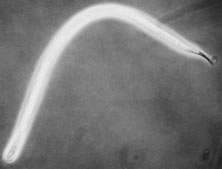

O. volvulus is one of a group of filarial nematodes. Other members include Wuchereria bancrofti and Brugia malayi, which produce lymphatic filariasis and elephantiasis and Loa loa, which causes loiasis. The adult worms live encysted in fibrous nodules, which may be single or conglomerate. Each nodule contains between two to three female worms lying in a twisted, tangled mass (hence the term volvulus). The adult female O. volvulus organism is a white threadlike worm, 30 to 70 cm long and only 0.3 mm across (Fig. 3). Adult males have a similar appearance but are thinner and much shorter (about 2.5 to 5 cm long).

Fig. 3. Adult worms of Onchocerca volvulus can be freed from excised nodules by collagenase digestion, which removes all of the host tissue. This nodule contained two adult females, which are much longer and thicker than the one male seen emerging at the upper right. These three worms were obtained from the same nodule.

Adult female worms have a life span of 8 to 10 years but may live up to 15 years. During their lifetime, each releases millions of first-stage larvae, also known as microfilariae. A microfilaria is 320 to 360 μm long and 5 to 10 μm in diameter (Fig. 4) and lives for 6 to 30 months.1,2 In hyperendemic areas, the total microfilaria load in the body of affected individuals may be as high as 150 million.4